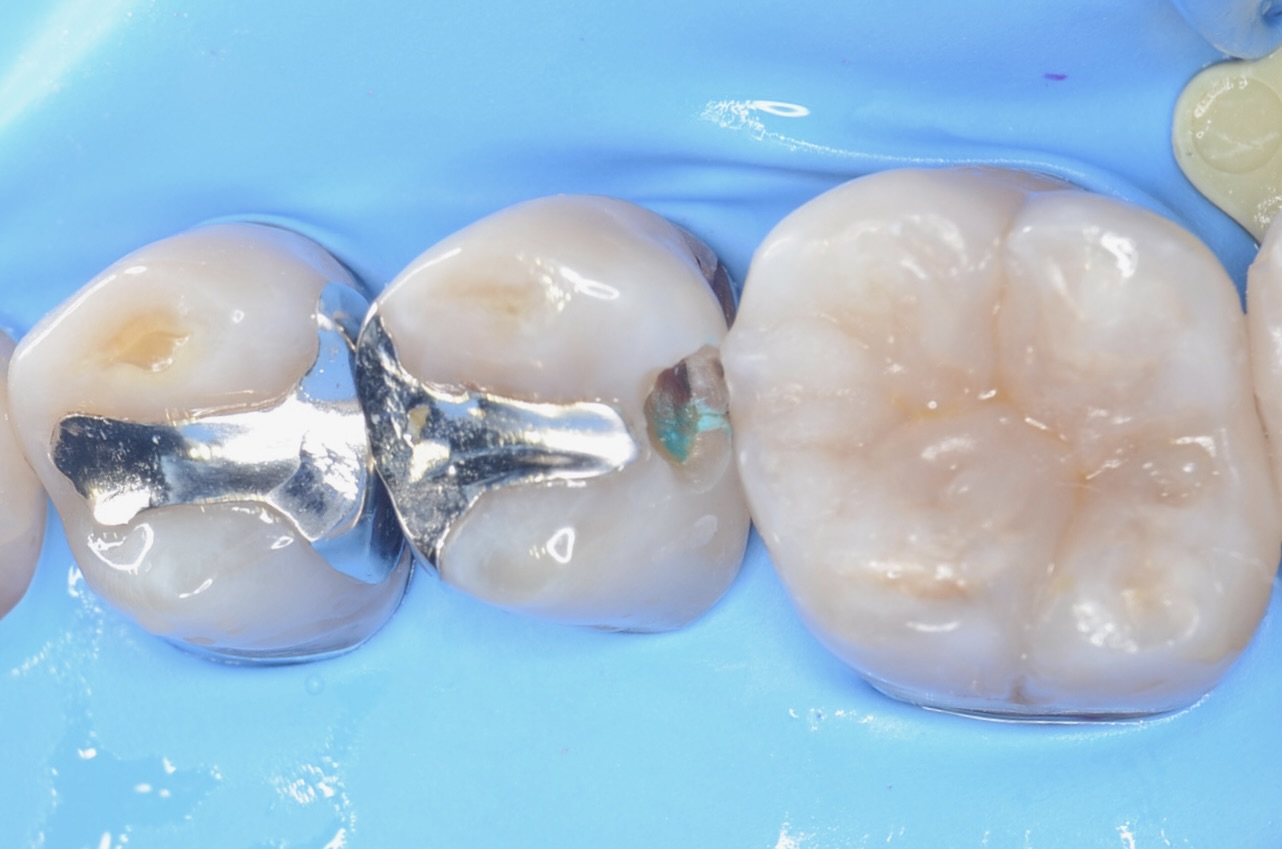

5番遠心

虫歯が広がっていました。 -

6番近心

6番の近親も虫歯でした。 -